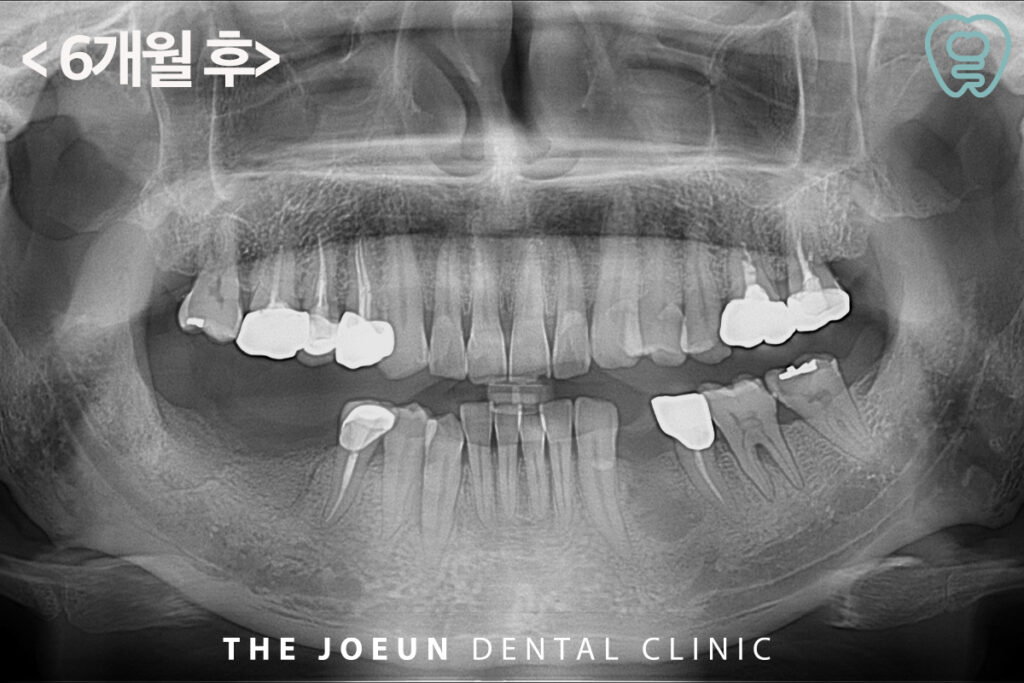

뼈이식을 하고 약 6개월 뒤, 검진 후 임플란트 식립을 진행하였습니다.

잇몸뼈가 심하게 파괴되어 걱정했지만 안정적으로 최종 보철물까지 완료하였습니다.